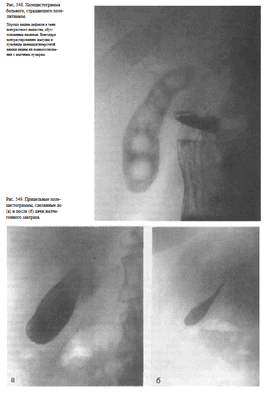

Рис. 539. Обзорный снимок (электрорентгенограмма) живота, выполненный в положении больного стоя.

Острая кишечная непроходимость. Хорошо видны раздутые газом петли кишечника с уровнями жидкости.